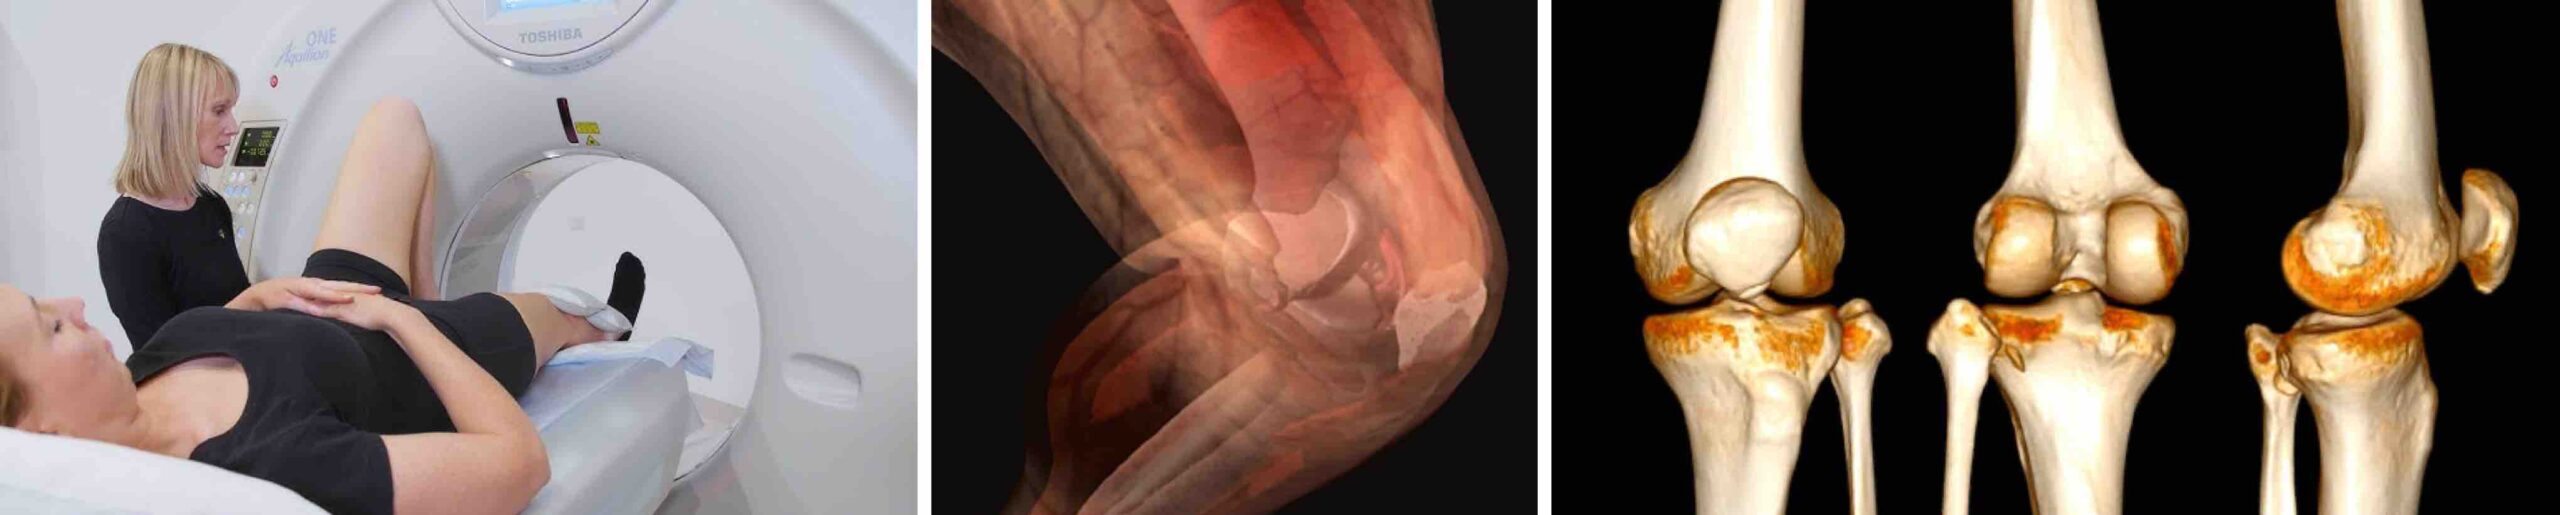

A tomografia computadorizada do joelho é um exame de imagem avançado, rápido e preciso, utilizado para avaliar com detalhes as estruturas ósseas e articulares dessa região do corpo. Graças à tecnologia de raios X em alta resolução, a tomografia permite visualizar cortes transversais e reconstruções tridimensionais, oferecendo informações fundamentais para diagnósticos ortopédicos e planejamentos cirúrgicos. A tomografia computadorizada do joelho é um exame de imagem frequentemente solicitado pelo médico ortopedista para analisar a articulação.

A tomografia computadorizada do joelho é um método de diagnóstico que utiliza radiação ionizante para gerar imagens em alta definição. Diferentemente do raio X comum, que mostra apenas uma projeção bidimensional, a tomografia cria imagens em camadas que permitem identificar alterações com muito mais precisão. Por isso, é um dos exames de imagem mais solicitados quando há suspeita de fraturas complexas, doenças articulares ou lesões estruturais.

O exame de tomografia computadorizada do joelho é um exame simples, indolor e rápido. Dura entre 5 e 15 minutos. O paciente deita-se na mesa do tomógrafo, que desliza suavemente enquanto o equipamento capta e gera as imagens. É comum que o técnico peça para o paciente manter a perna imóvel para garantir a qualidade das imagens. Em alguns casos, pode ser necessário o uso de contraste iodado, principalmente quando o médico deseja avaliar vasos sanguíneos ou investigar melhor processos inflamatórios.

As principais vantagens do exame de tomografia computadorizada do joelho são: alta precisão na detecção de fraturas e alterações ósseas, rapidez ( ideal para casos de emergência ), possibilidade de reconstrução tridimensional e excelente visualização de estruturas que não aparecem bem em outros exames de imagem.